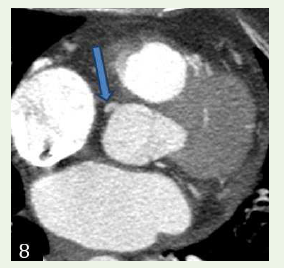

Case 4: A 68-year-old female with c/o chest pain, case of hypercholesterolemia and diabetes and concentric le ventricular hypertrophy in echocardiogram, demonstrated an anomalous origin of Left circumflex artery from the right coronary sinus with retro- aortic course.

Figure 8: Case 4: Maximum intensity projection reconstruction and 3D

volume rendered reformation shows an anomalous origin of Left circumflex

artery from the right coronary sinus with retro-aortic course.